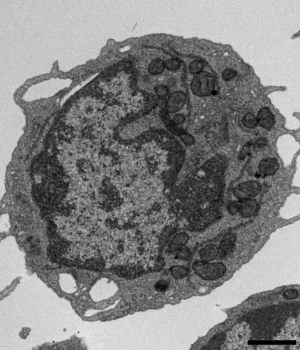

Técnicas adicionais fornecem insights mais profundos, incluindo citometria de fluxo, expansão ex vivo, RNA-seq, cromatina-seq acessível por transposase, imagens de alta resolução, ensaios metabólicos e estudos detalhados de mitocôndrias. Juntos, esses métodos permitem aos pesquisadores examinar como o MLKL afeta os HSCs em vários níveis.

Quando ativado sob estresse, o MLKL move-se brevemente para as mitocôndrias, as estruturas que geram energia dentro da célula. Lá, causa danos ao reduzir o potencial da membrana, alterar a estrutura mitocondrial e reduzir a produção de energia. Esses efeitos levam a características-chave da senescência nas HSCs, incluindo redução da capacidade de auto-renovação, redução da produção de células linfóides e uma mudança em direção à produção de células mieloides.